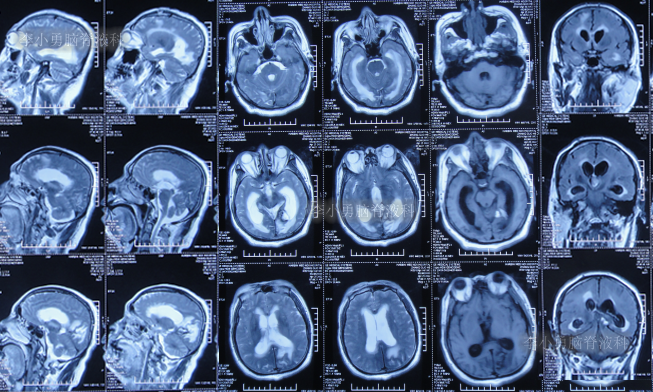

但出院回家后半个月即2022年4月18日,再次出现嗜睡,言语有时混乱,有走路不稳的症状,持续1周并没有好转反而逐渐加重,于是2022年4月25日(出院后22天),第2次返回给予手术的医院,查头颅核磁增强示脑积水(图-4);给予腰椎穿刺治疗。

图-4:2022年4月25日头颅核磁增强